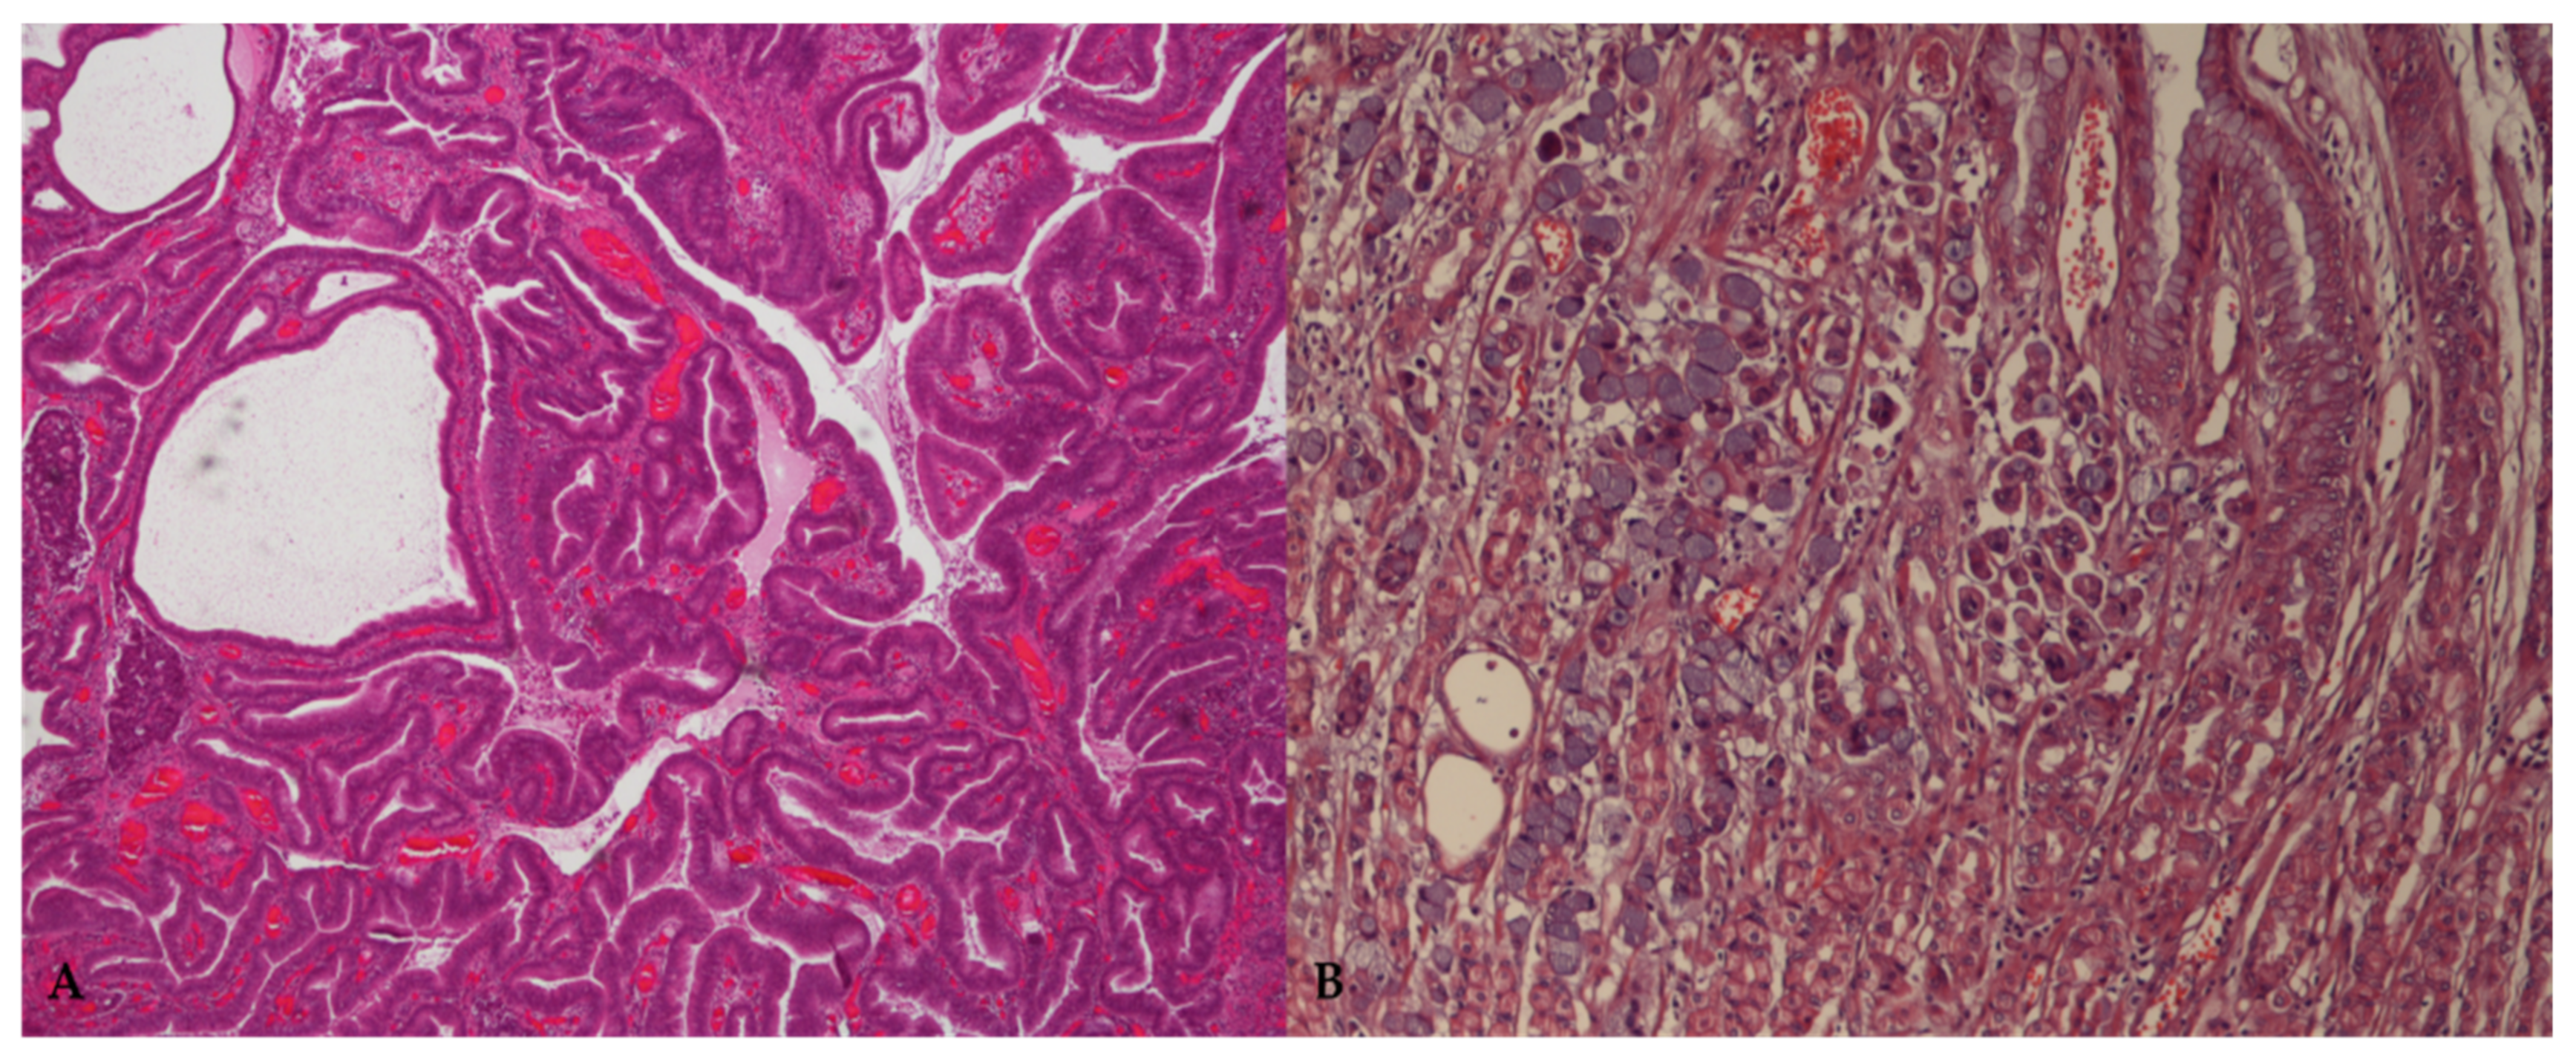

Microscopically, according with the WHO classification for domestic animals [22], carcinomas are categorized into papillary, tubular, mucinous, and signet ring cell subtypes, based on the main histological and cytological features of the lesion. In addition, Lauren’s criteria for humans have been successfully adapted to canine GC, placing carcinomas into two major histological subtypes, namely the intestinal and diffuse types [23] (Figure 1).

Figure 1.

Representative microphotographs of the main histological variants of canine gastric carcinoma. (A) Tubulopapillary or intestinal type, according to the WHO and Lauren classification, respectively. HE = 40×. (B) Signet ring cell carcinoma or diffuse type, according to the WHO and Lauren classification, respectively. HE = 100×.